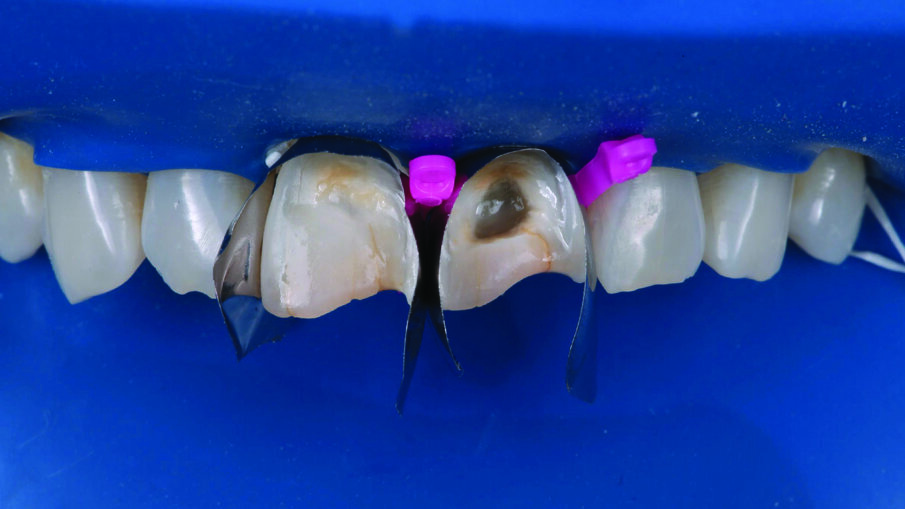

Two anterior matrices were placed to help create a natural anterior tooth shape and facilitate restoration of the interproximal and cervical margins.

A 1 mm layer of the Pink Opaquer (PO) was placed onto the discolored sclerotic dentin to mask dark areas and light cured for 20 seconds. The material offered a similar creamy handling as the body shades of 3M™ Filtek™ Universal Restorative.

Appearance of the teeth after the first application of 3M™ Filtek™ Universal Restorative A1 shade. No additional body shades were needed (to mask sclerotic dentin) when using the Pink Opaquer.